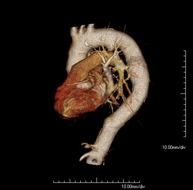

- Angio-TC aorta abdominal

Prueba diagnóstica no invasiva que consiste en el estudio de la arteria aorta abdominal obteniendo imágenes de alta definición anatómica mediante el empleo de un equipo de TC (Tomografía Computarizada) y de contraste yodado. La calidad de las imágenes permite realizar reconstrucciones en 2D y 3D gracias a estaciones de trabajo especializadas en el estudio arterial. Está indicado en aquellos pacientes con enfermedad vascular (aterosclerosis), en aneurismas de aorta, en pacientes con dolor abdominal de posible origen vascular, en estudios pre-quirúrgicos de lesiones adyacentes a la aorta abdominal como "mapa" vascular, etc. La información obtenida de forma no invasiva es indispensable para los pacientes que requieren tratamiento percutáneo o quirúrgico. En aquellos pacientes que solo requieren un seguimiento de las lesiones vasculares, esta técnica es la técnica no invasiva de elección junto con la angio-RM.

Prueba diagnóstica no invasiva que consiste en el estudio de la arteria aorta abdominal obteniendo imágenes de alta definición anatómica mediante el empleo de un equipo de TC (Tomografía Computarizada) y de contraste yodado. La calidad de las imágenes permite realizar reconstrucciones en 2D y 3D gracias a estaciones de trabajo especializadas en el estudio arterial. Está indicado en aquellos pacientes con enfermedad vascular (aterosclerosis), en aneurismas de aorta, en pacientes con dolor abdominal de posible origen vascular, en estudios pre-quirúrgicos de lesiones adyacentes a la aorta abdominal como el "mapa" vascular, etc. La información obtenida de forma no invasiva es indispensable para los pacientes que requieren tratamiento percutáneo o quirúrgico. En aquellos pacientes que solo requieren seguimiento de las lesiones vasculares, esta técnica es la técnica no invasiva de elección junto con la angio-RM.